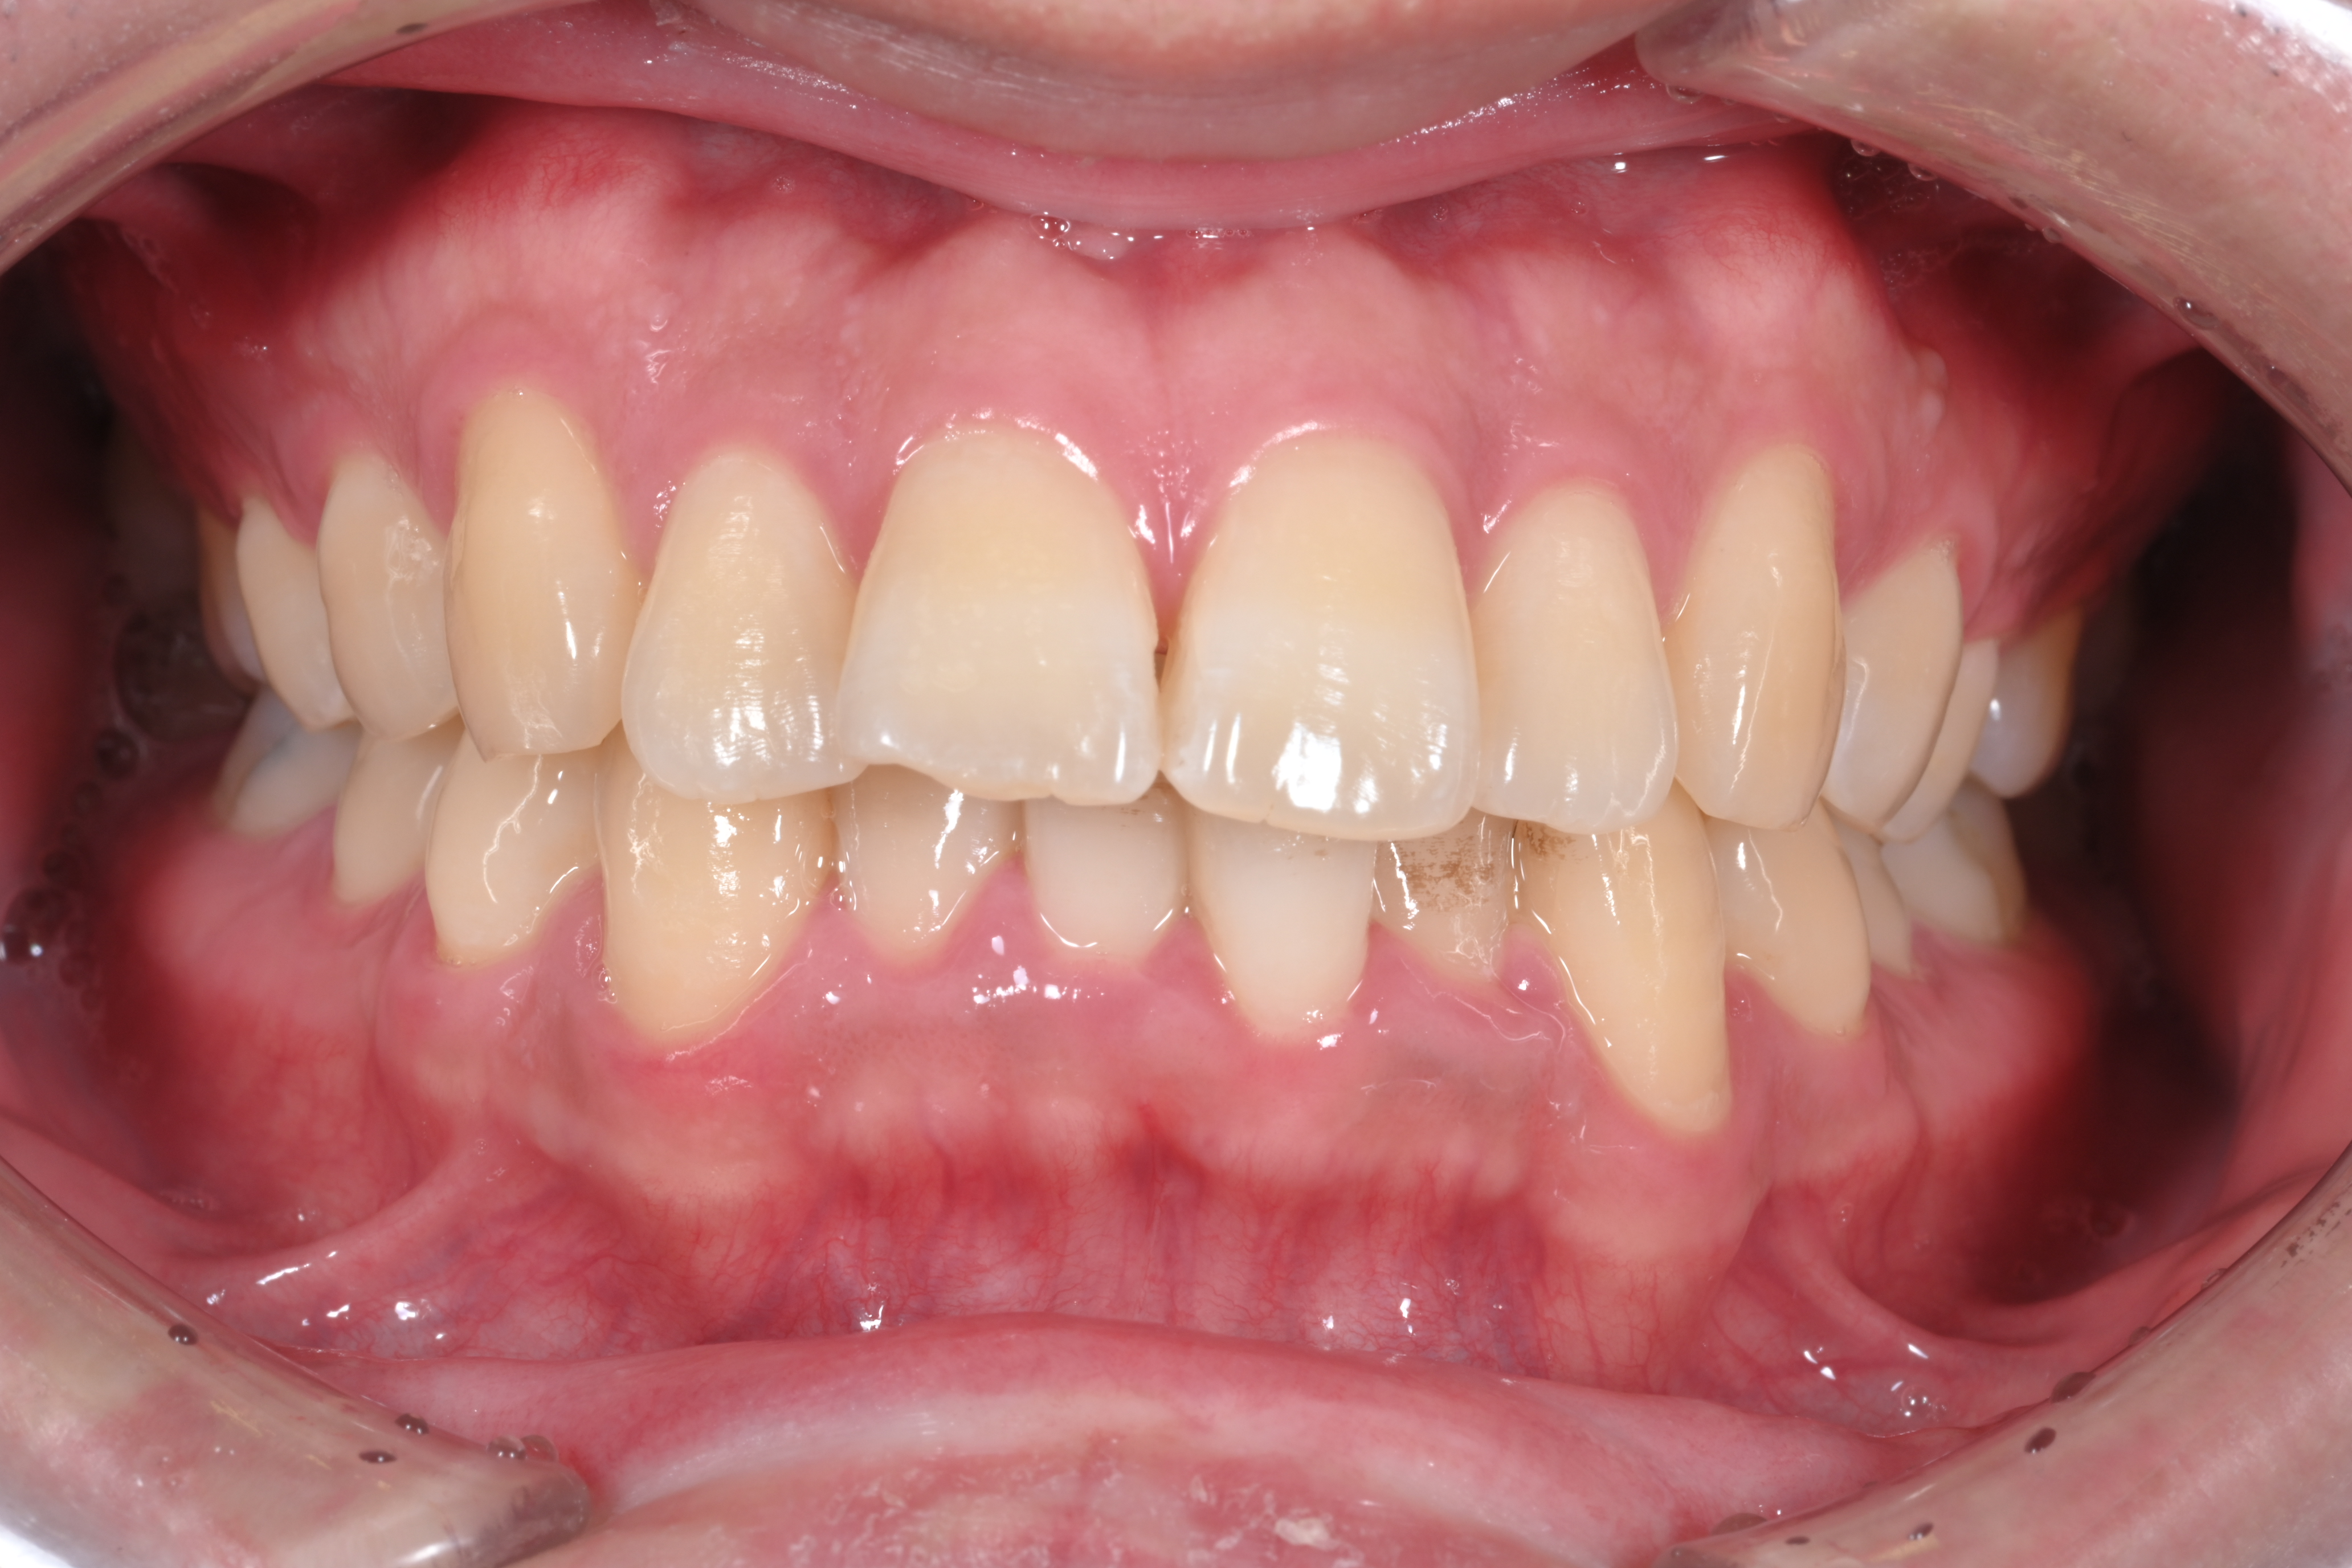

下顎前歯部の叢生(下の前歯のガタガタ)を主訴に来院された方の矯正治療について

主訴 下の前歯がガタついているのが気になる

初診時の画像

今回はギリギリのところですね。上の歯に関しては確実に部分矯正で可能ですが、下の歯に関してはガタガタ度が強く全体の矯正をおすすめします。一部分の矯正だけ行う程度では完全に並びきらない可能性がありますね。

今回は下顎前歯部の叢生を気にされてご来院されました。部分矯正のみで治療が可能か全体の矯正が必要かは患者様では判断できないと内容です。歯並びでお悩みの方は、まず実歯科医院で自分の歯並びがどの程度悪いのか診断してもらう必要性があります。それにより治療費や治療期間などが大きく変わってきます。